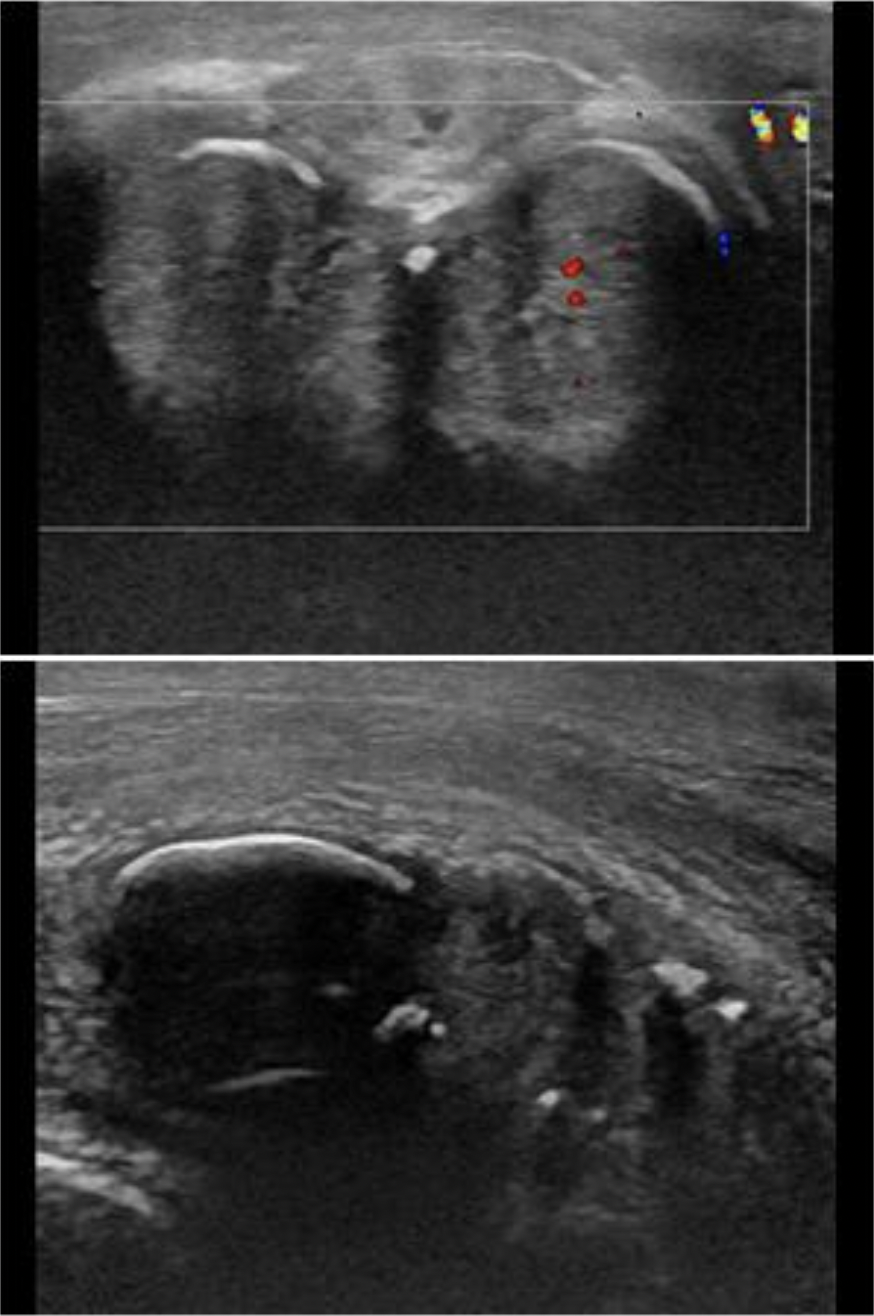

A 2yr old presents with a swollen abdomen and pain for 3 days. The doctor suspects an intussusception is present. How will this appear on the exam?

B. prominent focal area of concentric rings of bowel

An intussusception refers to a segment of bowel that involutes into itself. You will see a focal area of concentric rings of bowel that do not persitalse or change shape.

A 3yr old is scanned due to vomiting and a palpable lump in the abdomen.

These findings are most suggestive of:

C. Intussusception

The image demonstrates intussusception with the the inversion of one portion of the intestine within another. Note the body marker indicates the area of interest is on in the mid to lower quadrant on the left side. The aorta is also visualized on the image. Pyloric stenosis is diagnosed in early infancy and would be located in the epigastric/RUQ area. The aorta would not be demonstrated in the area of the appendix.